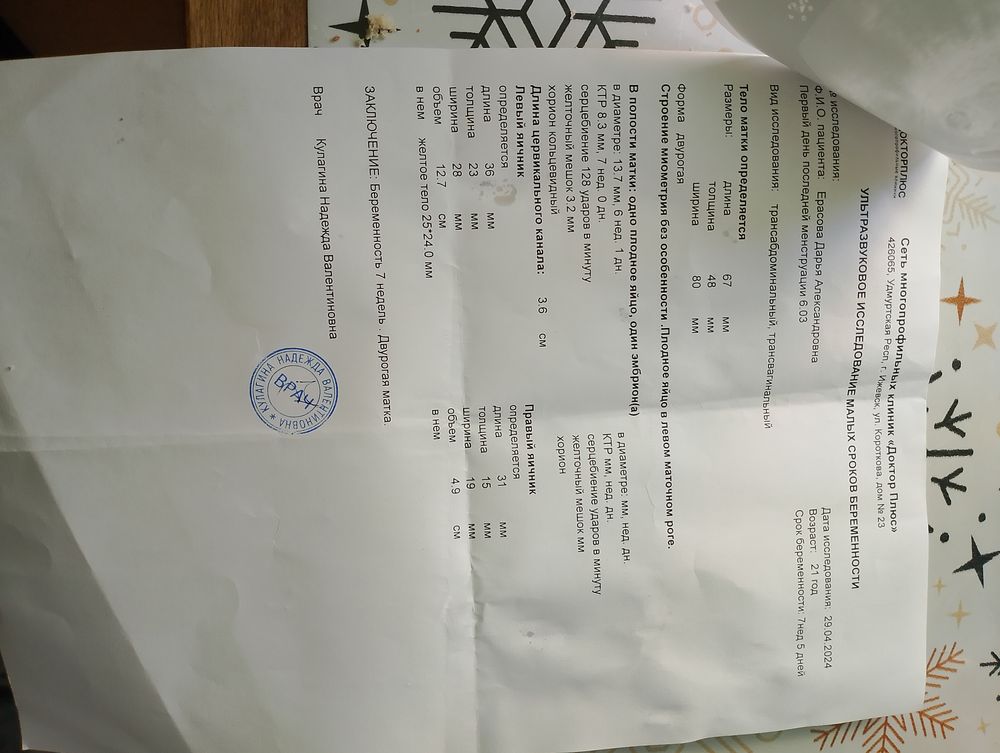

Девочки, эмбрион растёт, а плодное яйцо нет.

Девочки, эмбрион растёт, а плодное яйцо нет.

У вас все еще сохраняется 5 мм между КТР и ПЯ. Это та самая минимальная разницы. Может разогнаться. Только ждать, пока что не понятно и никто не даст точных прогнозов.